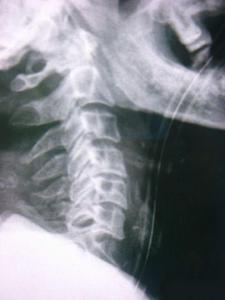

因?yàn)轭i骨骨折也就是頸部脊椎骨的骨 折,在脊椎骨中央有神經(jīng)通過,這些神經(jīng)像電纜一樣能把大腦的命令傳達(dá)到全身,又能把身體的感覺傳向大腦。如果骨折切斷或壓迫脊椎骨中的神經(jīng),頸以下就會(huì)完 全麻痹,有時(shí)會(huì)使呼吸停止。

3、頸椎骨折常見于跳水誤跳入淺游泳池,或從很高的地方墜落以及交通事故等。